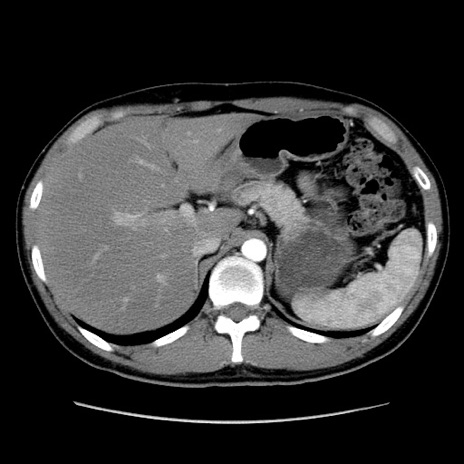

症例36(横断像)

【症例】20歳代 男性

【主訴】心窩部痛

【現病歴】今朝より上腹部痛あり。一旦軽快していたが再度出現したため救急要請。昨日夕に白身の魚を含む刺身を食べた。

【身体所見】BP 136/89mmHg、HR 74/min、BT 37.0℃、腹部:膨満、軟、心窩部に圧痛あり。反跳痛なし、筋性防御なし、腸雑音やや亢進あり。

【データ】WBC 17700、CRP 0.48